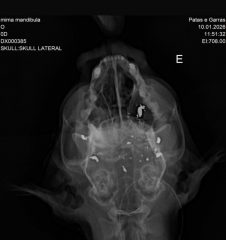

Segundo a entidade, o animal foi atingido por três disparos na região da cabeça. Dois tiros causaram a destruição da mandíbula e o terceiro atingiu o céu da boca, provocando ferimentos considerados fatais.